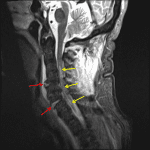

Indication: Trauma, jumped facets at C6-C7 and C4 left lamina and spinous process fracture on prior CT

- Mild residual anterolisthesis at C6-C7 with widening of the anterior disc space and disruption of the anterior longitudinal ligament, the posterior longitudinal ligament, and the ligamentum flavum at this level

- Additional disruption of anterior longitudinal ligament at the level of C4-C5 as well as possible focal disruption of the posterior longitudinal ligament at C4-C5 and possible focal ligamentum flavum disruption at C3-C4

- T2/STIR signal hyperintensity in the central aspect of the spinal cord extending from C3-C4 through C6-C7

- T2/STIR signal hyperintensity in the bilateral C6-C7 facet joints

- Extensive T2/STIR signal hyperintensity in the interspinous ligaments and supraspinous ligament from the skull base through C6-C7

- Prevertebral soft tissue thickening and T2/STIR signal hyperintensity throughout the cervical spine extending into the upper thoracic spine

- T2/STIR signal hyperintensity in the C4 left lamina and spinous process

- Multilevel posterior disc osteophyte complexes, facet hypertrophy, uncovertebral spurring, and ligamentum flavum thickening contribute to advanced spinal canal stenosis from C4-C5 through C6-C7 and varying degrees of multilevel neural foraminal stenosis, severe bilaterally from C4-C5 through C6-C7

- Cord contusion, ligamentous injury

Mild residual anterolisthesis at C6-C7 with widening of the anterior disc space, evidence of bilateral facet capsular injury, and disruption of the anterior longitudinal ligament, the posterior longitudinal ligament, and the ligamentum flavum at this level. Additional disruption of anterior longitudinal ligament at the level of C4-C5 as well as possible focal disruption of the posterior longitudinal ligament at C4-C5 and possible focal ligamentum flavum disruption at C3-C4.

T2/STIR signal hyperintensity in the central aspect of the spinal cord extending from C3-C4 through C6-C7 concerning for cord contusion.

Extensive ligamentous injury involving the interspinous ligaments and supraspinous ligament from the skull base through C6-C7.

T2/STIR signal hyperintensity in the C4 left lamina and spinous process, corresponding with the known fractures.

Prevertebral soft tissue edema throughout the cervical spine extending into the upper thoracic spine.

Background of advanced degenerative changes with multilevel posterior disc osteophyte complexes, facet hypertrophy, uncovertebral spurring, and ligamentum flavum thickening contribute to advanced spinal canal stenosis from C4-C5 through C6-C7 and varying degrees of multilevel neural foraminal stenosis, severe bilaterally from C4-C5 through C6-C7.